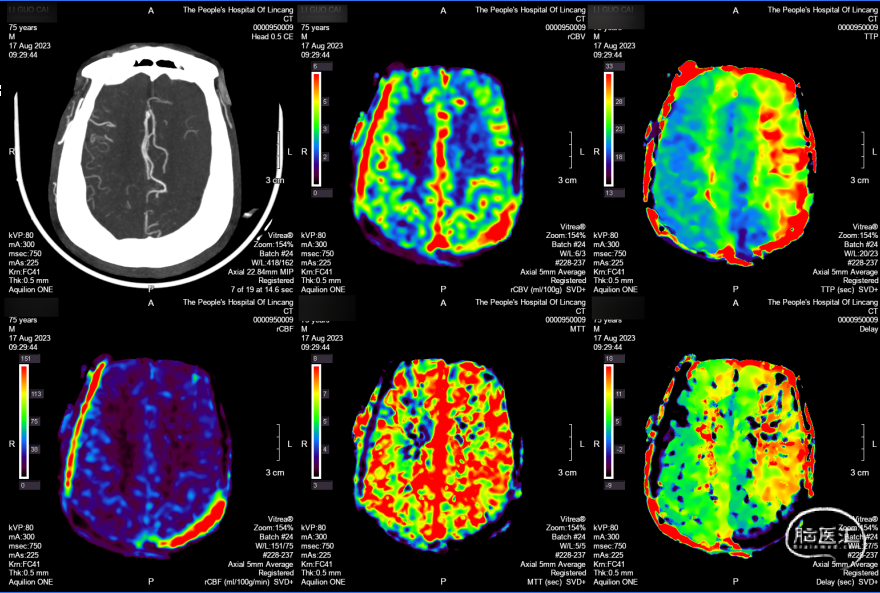

CTP:左侧大脑半球大面积TTP及MTT延长,CBV左侧大脑半球大面积TTP及MTT延长,rCBV基本正常或轻度下降,rCBF下降,符合脑梗死前期Ⅱ1期表现。